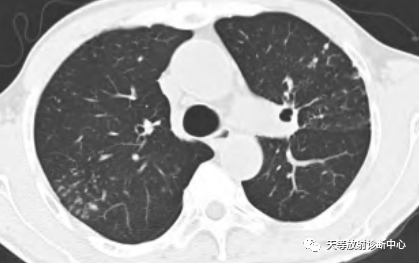

影像学表现:整体观察肺内多发病灶,散在分布,病灶的主要形态为:多发大小不等肺气囊、多发结节共同存在。

1、肺气囊大小不等,张力较大,圆形膨胀感强,周围可见大小不等结节影;

2、病灶主要沿支气管血管束方向分布,部分病灶达到胸膜下;

3、支气管间质增厚;

4、结节影大小不等,小的呈树芽征堆积,大的部分到达胸膜小,具有糊墙征,性格较温和。仔细观察病灶呈四边形、多边形,边缘刀切感,边界模糊。